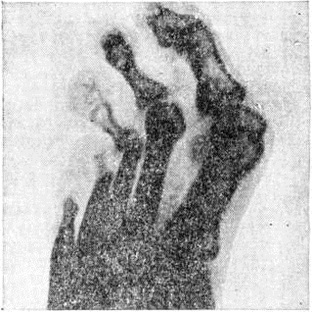

Рис. 4. | ||

При туберкулой дном типе (ТТ) очаговая деструкция костной ткани встречается довольно редко. Явления остеолиза (смотри полный свод знаний) как следствия нервно-трофических и сосудистых нарушений наблюдаются при всех типах Лепра, сопровождающейся полиневритами. Вначале эти изменения проявляются сглаженностью ногтевых отростков, расширением каналов, питающих кость, а в более поздних стадиях — ведут к мутиляции фаланг кистей и стоп. Концентрическая атрофия фаланг, являющаяся одним из характерных признаков Лепра, вызывает своеобразную деформацию костей в виде шахматной пешки (рисунок 7).

Резорбция костей может вести к патологический переломам, подвывихам, вывихам, анкилозам, частичному или полному отторжению костей (рисунок 8). Изменения в костях стоп обычно более выражены вследствие присоединения остеомиелита, вызывающего секвестрацию, деструкцию костей, и ведут к глубокой инвалидности больного. Встречаются также периоститы и гиперостозы плюсневых, метакарпальных, реже длинных трубчатых костей предплечий и голеней.